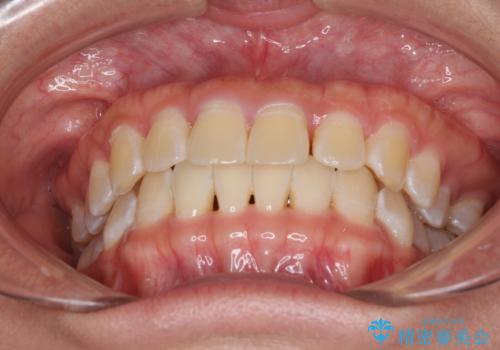

前歯の隙間と上下正中のズレを解消

- 上下前歯隙間と正中のズレを改善したいとのことで来院された患者様です。

自己管理を減らしたいとのことで、ワイヤー装置による矯正治療を行うこととしました。

正中がなかなか合わずに、2年近くの治療期間を要しました。